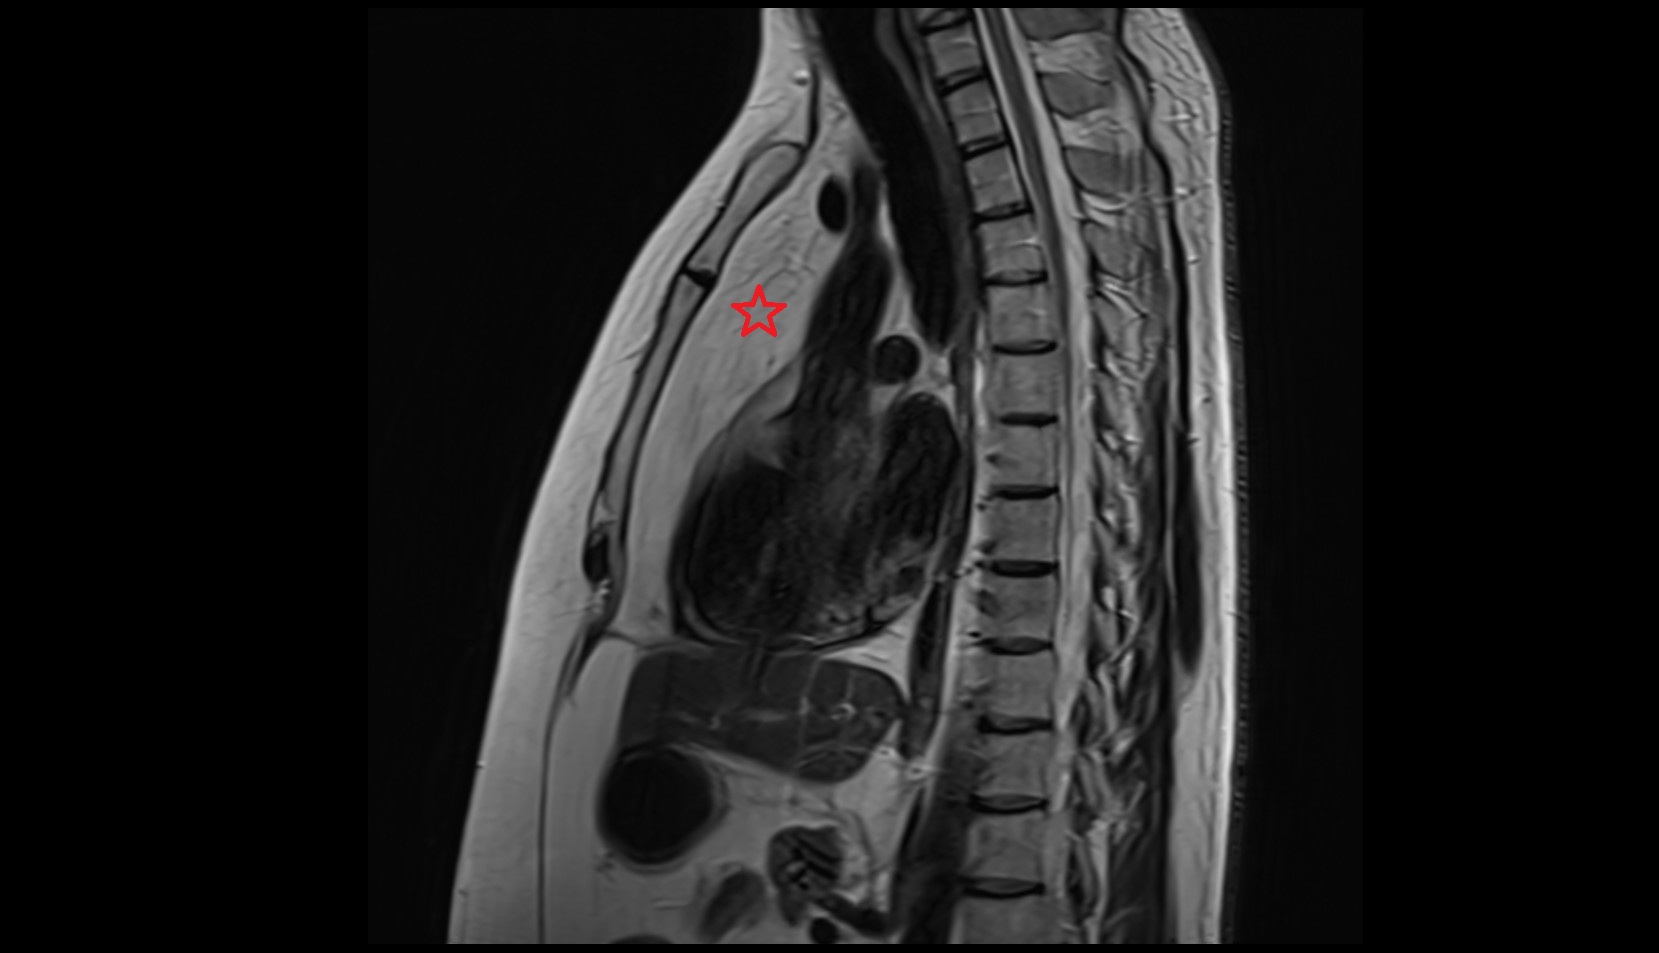

- Placenta

- Uterus (pregnancy)

- Amniotic fluid

- Umbilical cord

- Urinary Bladder in Pregnancy

- Cervix in Pregnancy

- Vagina in Pregnancy

- Fundus of uterus in pregnancy